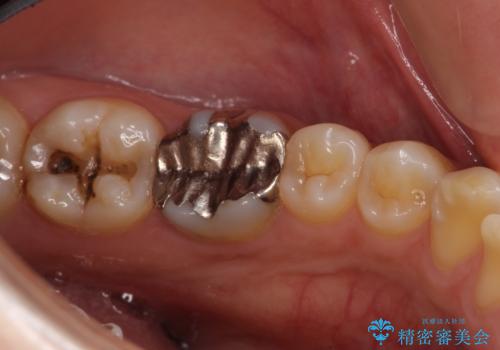

- 左下奥歯の銀歯のつめものがとれたことを主訴にご来院された患者様です。

1番奥の歯のセラミック治療をご希望されましたが、レントゲンなどの診査の結果、大きな虫歯などもありませんでした。

それよりも奥から2番目の歯のほうが、適合不良の銀のつめものが入っており、大きな虫歯が疑われました。

虫歯の大きさや形を加味して、1番奥を保険治療、奥から2番目をセラミック治療で行うことになりました。